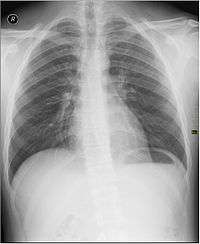

Projection (plain) radiography

Radiographs (originally called roentgenographs, named after the discoverer of X-rays, Wilhelm Conrad Röntgen) are produced by transmitting X-rays through a patient. The X-rays are projected through the body onto a detector; an image is formed based on which rays pass through (and are detected) versus those that are absorbed or scattered in the patient (and thus are not detected). Röntgen discovered X-rays on November 8, 1895 and received the first Nobel Prize in Physics for their discovery in 1901.

In film-screen radiography, an X-ray tube generates a beam of X-rays, which is aimed at the patient. The X-rays that pass through the patient are filtered through a device called an grid or X-ray filter, to reduce scatter, and strike an undeveloped film, which is held tightly to a screen of light-emitting phosphors in a light-tight cassette. The film is then developed chemically and an image appears on the film. Film-screen radiography is being replaced by computed radiography (CR) but more recently by digital radiography (DR) and the EOS imaging.[1] In the two latest systems, the X-rays strike sensors that converts the signals generated into digital information, which is transmitted and converted into an image displayed on a computer screen. In digital radiography the sensors shape a plate, but in the EOS system, which is a slot-scanning system, a linear sensor vertically scans the patient.

Plain radiography was the only imaging modality available during the first 50 years of radiology. Due to its availability, speed, and lower costs compared to other modalities, radiography is often the first-line test of choice in radiologic diagnosis. Also despite the large amount of data in CT scans, MR scans and other digital-based imaging, there are many disease entities in which the classic diagnosis is obtained by plain radiographs. Examples include various types of arthritis and pneumonia, bone tumors (especially benign bone tumors), fractures, congenital skeletal anomalies, etc.